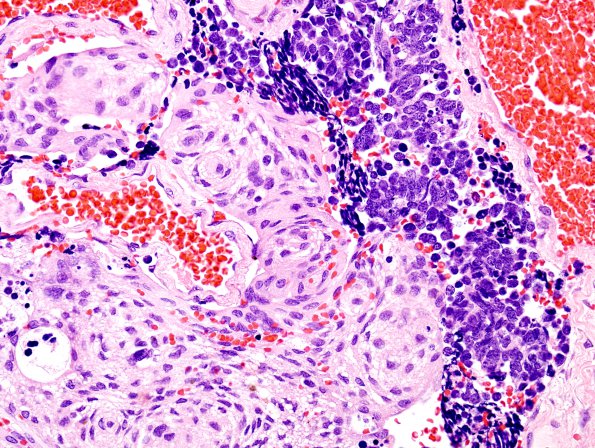

Washington University Experience | NEOPLASMS (METASTASES) | Metastasis - to - Tumor | 1B5 Meningioma with SCLC metastasis (Case 1) H&E 10

The tumors differ consistently in histologic appearance, representing a lung cancer metastasis to a meningioma. (H&E).